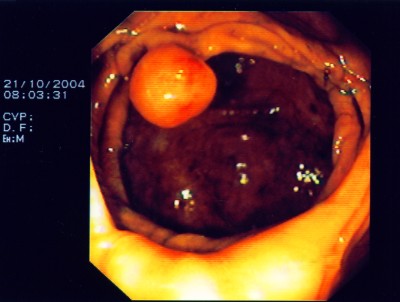

Großer Polyp des Dickdarmes